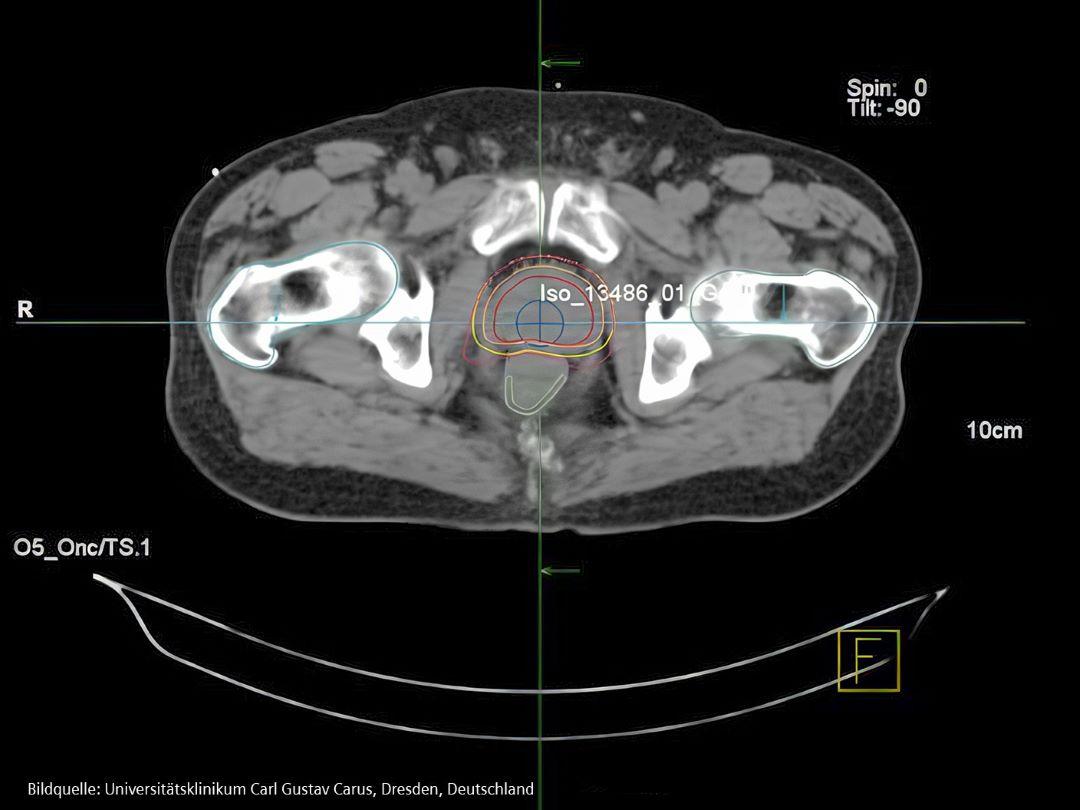

Bild von Varian Eclipse Intensity Modulated Radiotherapy Plan für Prostatakrebs-Patient

IMRT is advanced radiation therapy that targets tumors with adjustable beams, minimizing damage to healthy tissue and reducing side effects.

Die Strahlentherapie (auch Radiotherapie, RT) ist eine Krebsbehandlung, bei der hochenergetische Röntgenstrahlen oder andere Arten von Strahlung eingesetzt werden, um Krebszellen abzutöten oder ihr Wachstum zu verhindern. Es gibt verschiedene Arten der Strahlentherapie:

Die externe Strahlentherapie, die häufigste Form der RT, verwendet hochenergetische Röntgenstrahlen, um Krankheiten gezielt zu behandeln. Das hochentwickelte Gerät, das die Strahlentherapie durchführt, heißt Linearbeschleuniger oder kurz "Linac".